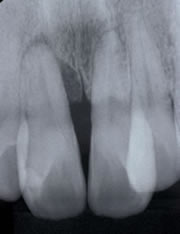

初診時、歯根の先まで歯槽骨吸収が認められ、排膿や出血があり、グラグラした歯でしたが、ケースによっては通常の治療で上記のような回復を確認出来る事があります。

特別な再生療法外科処置をしたわけではなく、原因の除去(歯垢・歯石除去)、根の治療、かみ合わせの調整など通常の歯周治療を実施した結果です。このように初診時の時には「保存は苦しいかな?抜歯かな?」と思っていても、歯周病治療に非常によく反応する場合もありますので、当医院では重度歯周病で保存が苦しそうな歯でもまず保存治療を試みるようにしています。その後、再評価(歯周病治療の反応を確認するステップ)しその歯が保存出来るか否か最終決定致し患者様に御相談しています